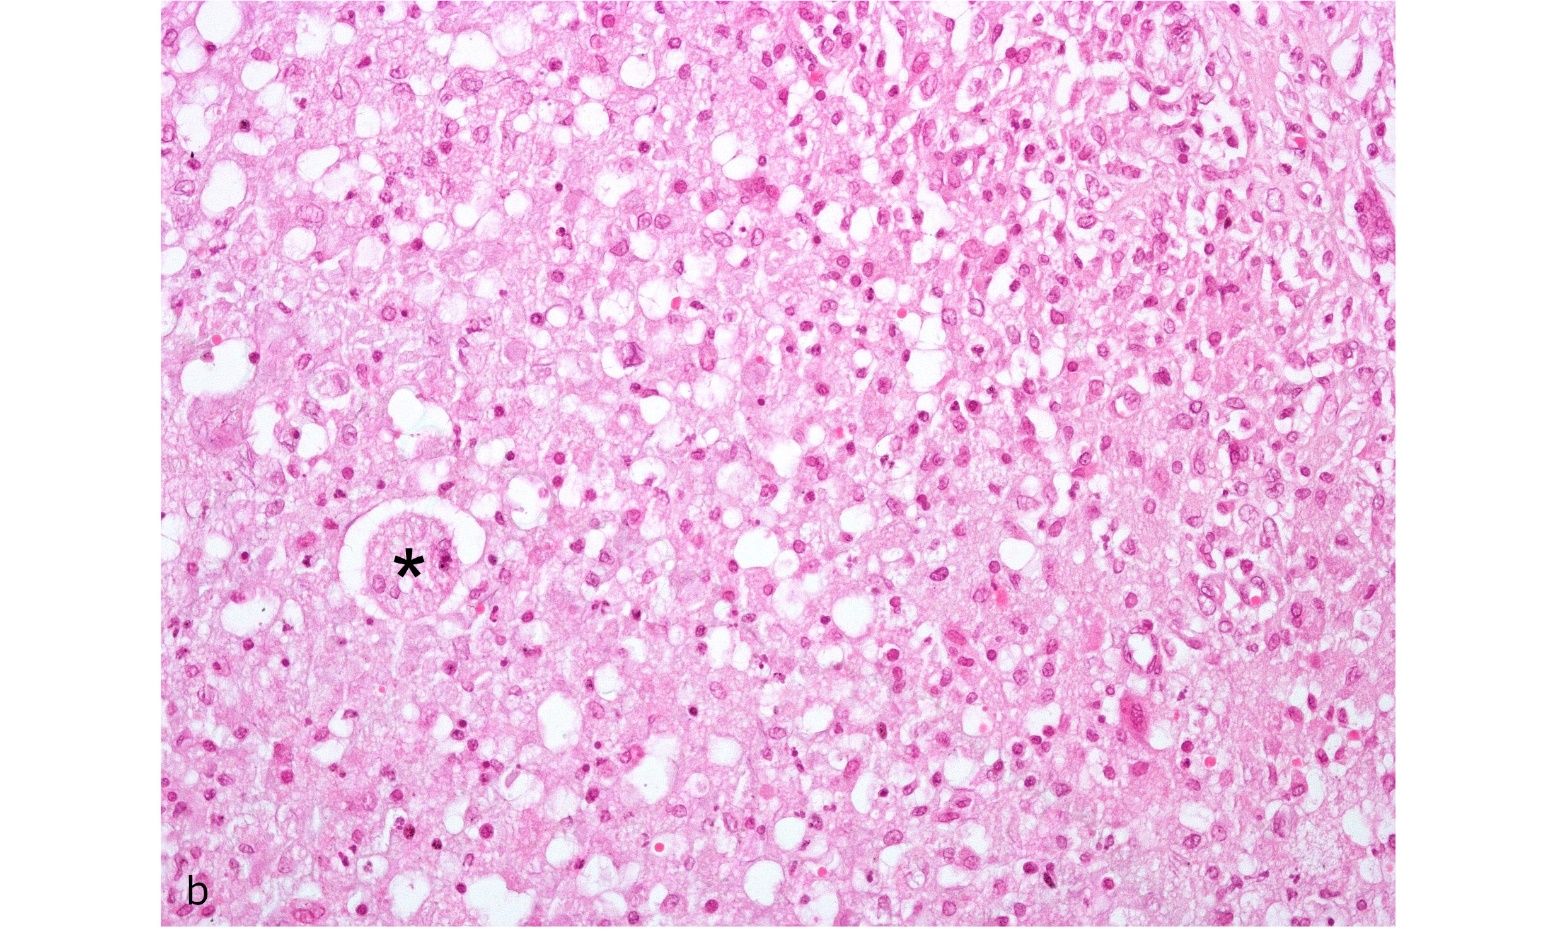

Figure. 2a. Testicle: Interstitial infiltration of eosinophilic material with macrophages, lymphocytes and few neutrophils composing granulomatous orchitis. Hematoxylin/eosin, 40x magnification.

Figure. 2b. Testicle : Detail of boxed area in A showing giant cell (*) and granulomatous inflammatory infiltrate. Hematoxilin/eosin, 200X magnification.

Contrary to the results observed in rabbits (Fort et al. 2012) infected with B. suis biovar 1, the inoculated armadillos did not show macroscopic lesions. In the histopathological studies, lesions were observed only in the epididymis tail of armadillo (B1); this was identical to the lesions observed in domestic species (Foster, 2007). The presence of Brucella in the epididymis and the lesions found in one of the infected animals could be associated with infertility problems in affected armadillos. No histopathological changes were observed in organs from armadillos (A1, B2, B3, and B5) or changes were too minor (e.g., slight infiltration of neutrophils or lymphocytes) to be associated with the infection. However, isolation of B. suis from most organs corroborated the presence of infection in these animals. The discrepancy in the lesions between species could be related to a variation in the pathogenesis of the infection. Future studies are needed to determine the pathology associated with long-term infection of B. suis in armadillos.